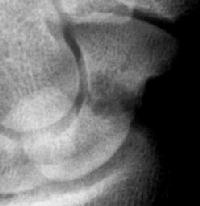

Late, with asymptomatic partial union or nonunion, but no haloing.

Click for larger image